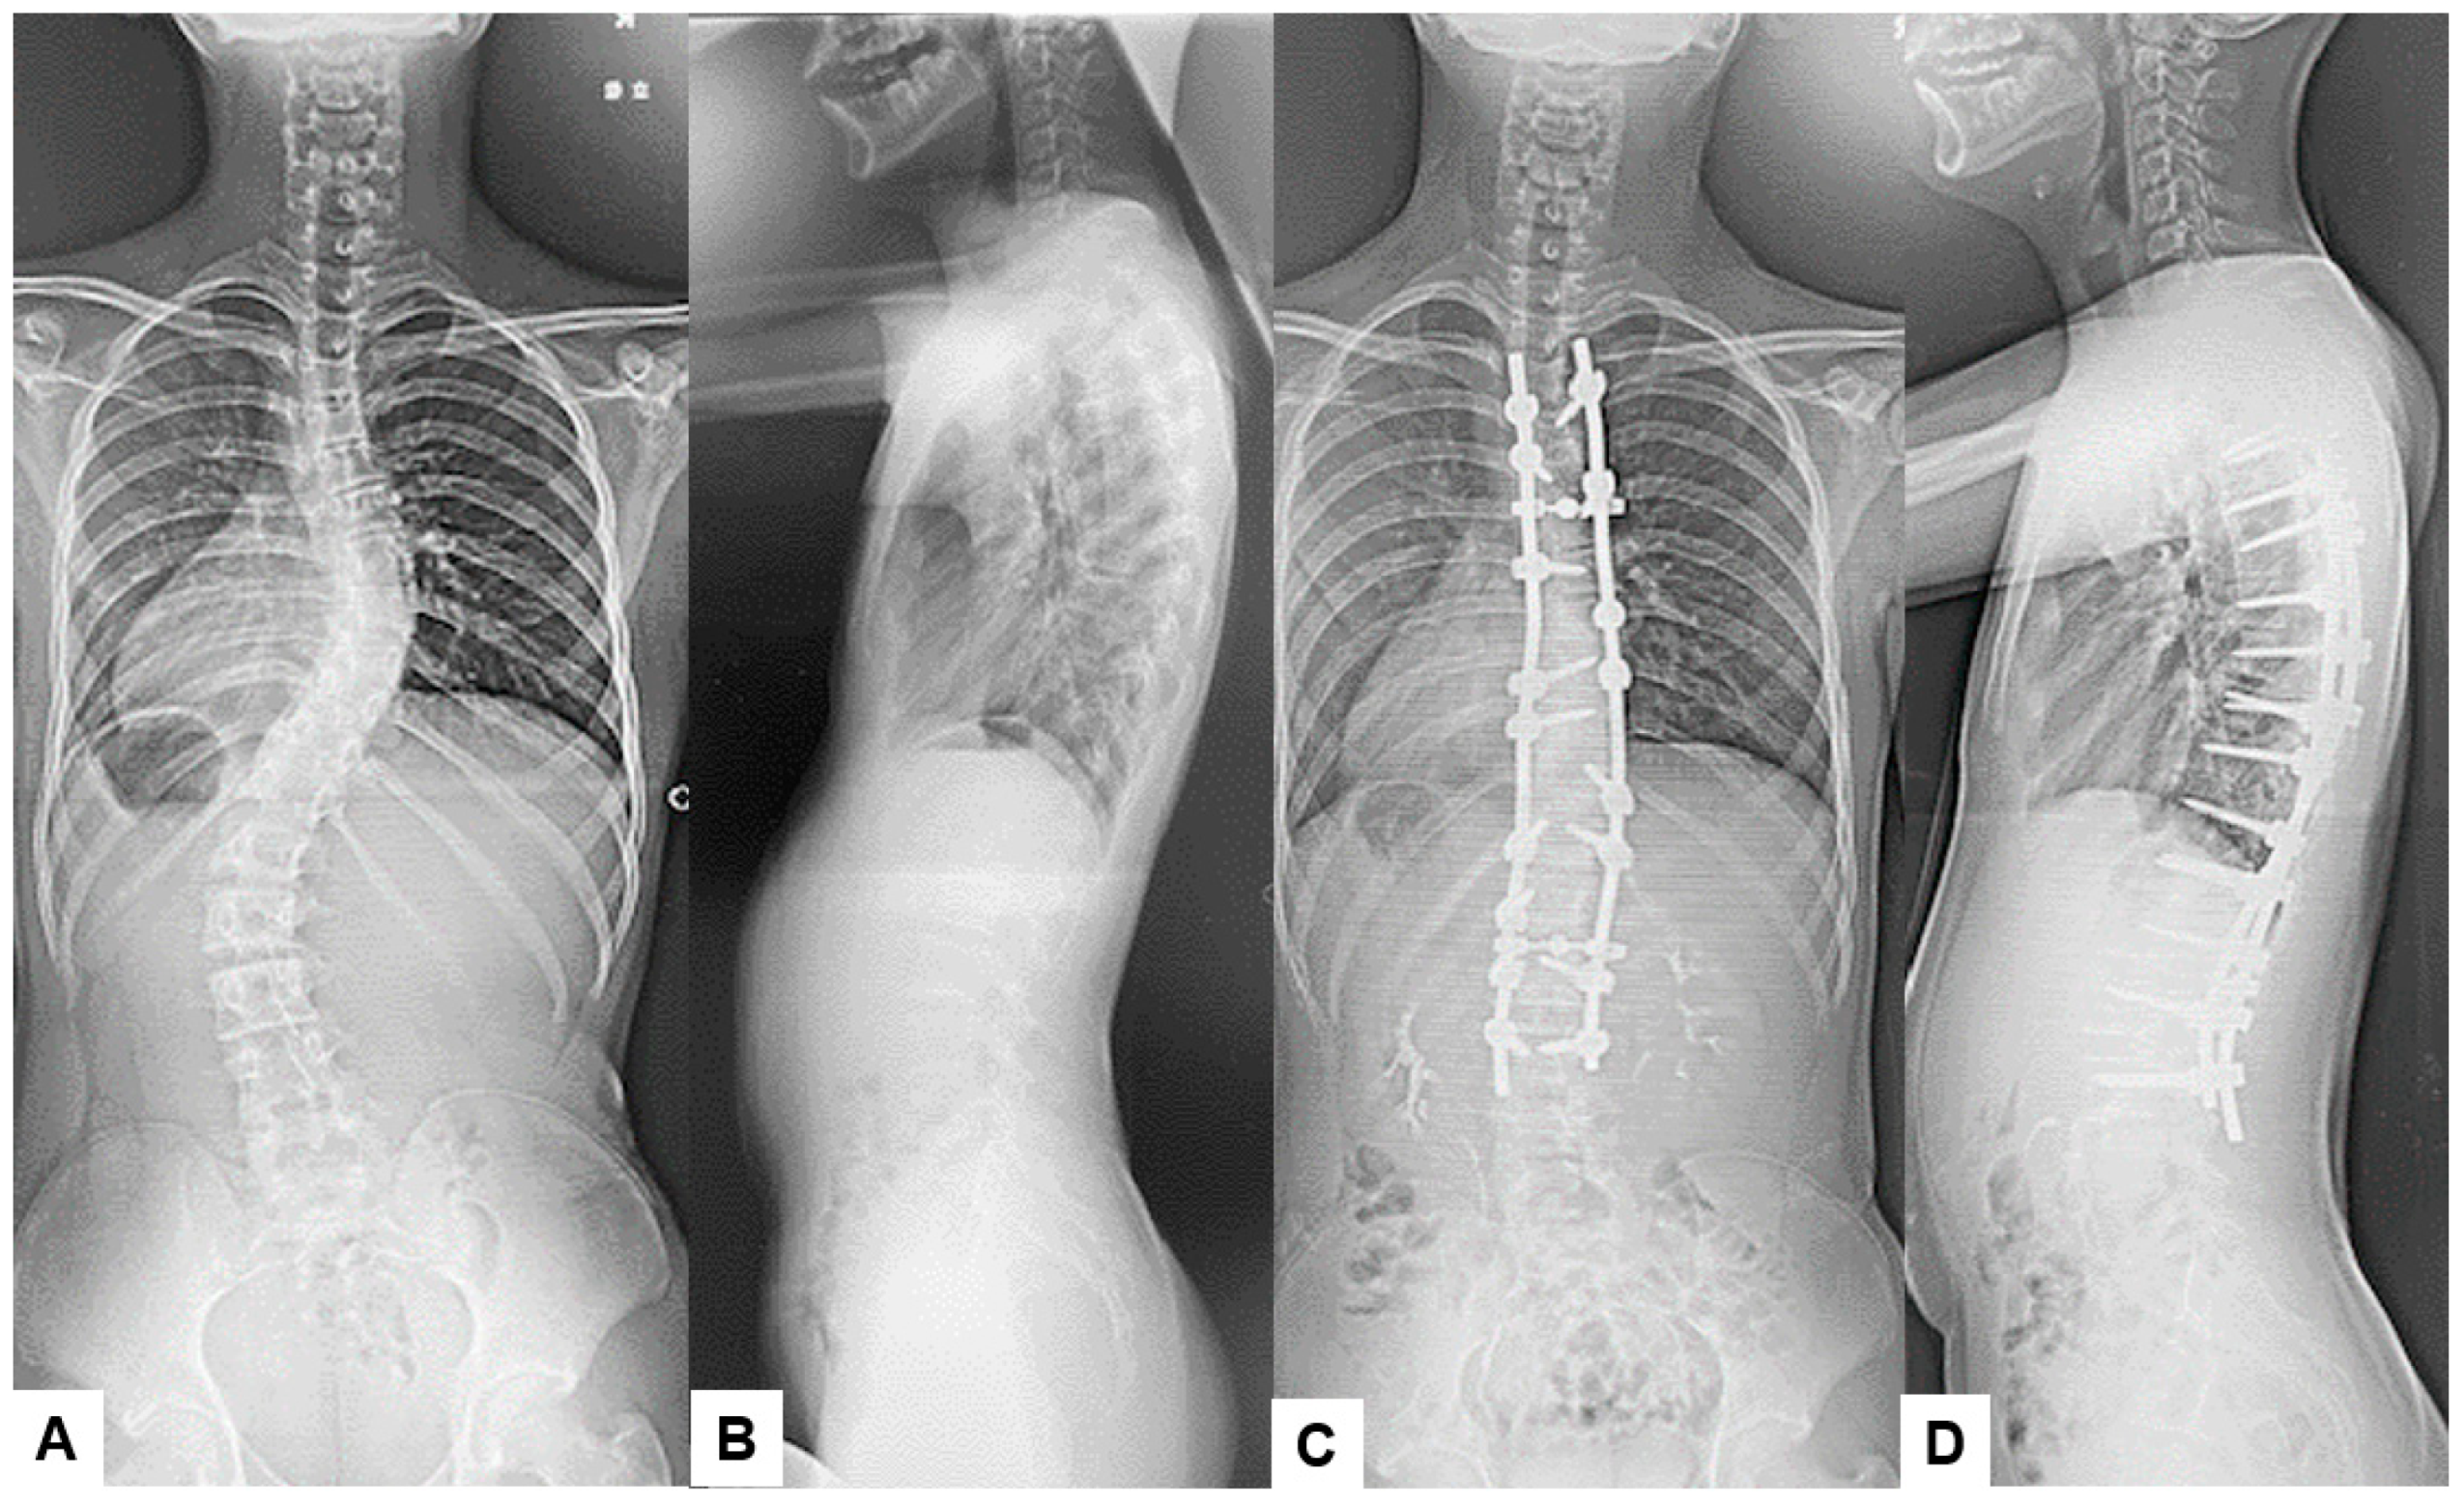

It is important to note that in our patient sample, no infections were observed in cases involving anterior approaches. This may be attributed to the minimal use of monopolar coagulation and reduced tissue disruption typically associated with anterior approaches. Additionally, our study reinforces the idea that certain types of surgeries, particularly multi-segmental fusions and scoliosis surgeries, may carry a higher risk of SSIs due to their complexity and longer operative times. Figure 3 and Figure 4 represent an example of a case undertaken at our institution for adolescent idiopathic scoliosis, in which the main surgical parameters played a major part in this scenario, and the extensive approach and long operative times resulting in SSI [13,16]. The correlation between extended surgical time and specific pathogens underlines the importance of surgical efficiency and robust perioperative management to mitigate infection risks in spine surgery. In a retrospective meta-analysis undertaken by Zhuo et al. with 22,475 patients, the evidence showed that posterior approaches had double the incidence (5% vs. 2.3%) over anterior approaches, and minimally invasive surgery had a much lower rate of infection (1.5% vs. 3.8%) [17].

Previous reports have emphasized both CE MRIs and CTs can help to identify the underlying microorganisms and differentiate the most frequent subtypes [18]. These image modalities can provide important features to diagnose infectious conditions and to avoid unnecessary biopsy and anti-bacterium treatments. Figure 3 and Figure 4 present the SSI after scoliosis correction surgery. It was a little difficult to use the MRI to evaluate SSI because of metal artifacts. However, enhanced CT revealed gas inside the abscess/effusion which is relatively specific to SSI (Figure 4).

Figure 3. 13 M, Adolescent idiopathic scoliosis, Posterior corrective fusion. (A) Preoperative spinal posteroanterior radiogram, (B) Preoperative spinal lateral radiogram, (C) Postoperative spinal posteroanterior radiogram, (D) Postoperative spinal lateral radiogram.